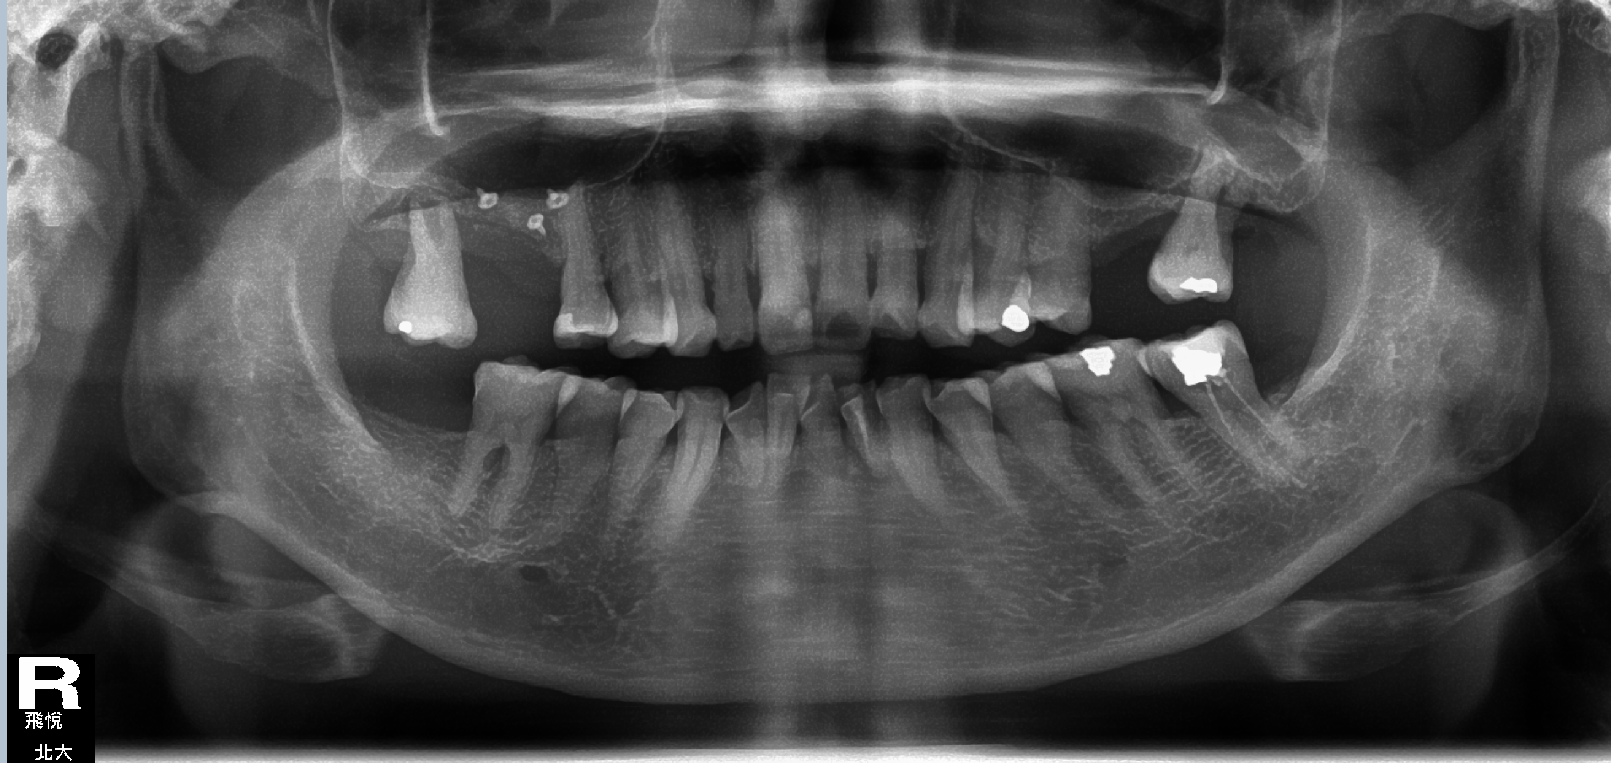

飛悅.北大牙醫聯合診所「從齒,我們想得比您更遠」 Beyond Dental Clinic 植牙+鼻竇增高手術**一次完成 首頁 診療項目 人工植牙 植牙+鼻竇增高手術**一次完成 案例分享 植牙+鼻竇增高手術~一次完成 看看我們的蘇醫師多麼專注的樣子~~ 其實手術沒有大家想像中的困難 今日手術時間才1小時喔! ×

植牙+鼻竇增高手術**一次完成 首頁 診療項目 人工植牙 植牙+鼻竇增高手術**一次完成 案例分享 植牙+鼻竇增高手術~一次完成 看看我們的蘇醫師多麼專注的樣子~~ 其實手術沒有大家想像中的困難 今日手術時間才1小時喔!